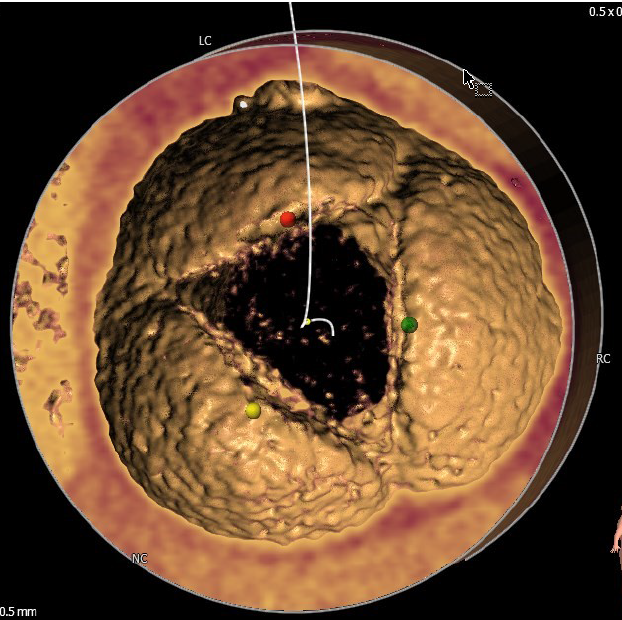

1.患者主动脉瓣三叶式,瓣叶基本等大,瓣膜增厚,瓣叶未见明显钙化。

2.患者主动脉瓣环周长折算直径约25.6mm。

3.患者双侧冠脉开口高度可LCA:17.2mm,RCA:24.6mm。

瓣环直径:25.6mm

左冠脉开口高度:17.2mm

右冠脉开口高度:24.6mm

瓣环、瓣叶无钙化

主动脉根部角度:80°

升主动脉与主动脉窦部夹角:106°